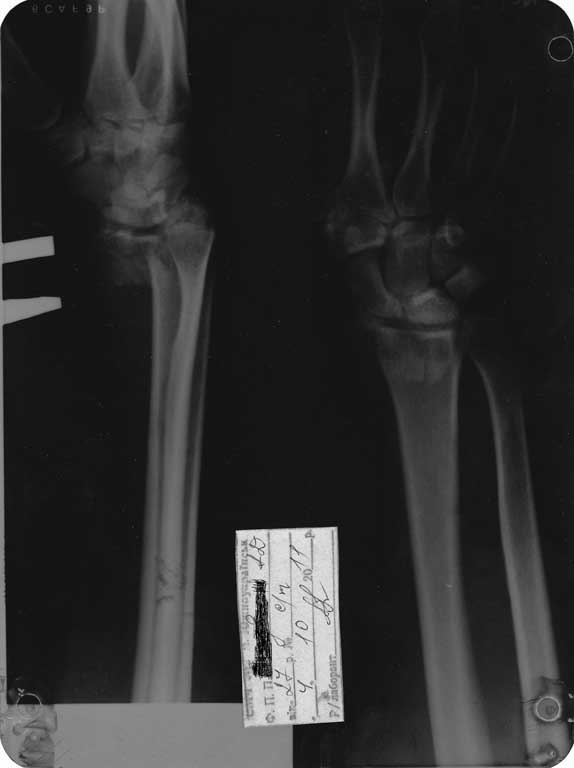

Давность травмы- неделя.

Интересует доступ, рекомендуемые фиксаторы.

Если есть,то примеры на снимках.

Скорей всего у Вашего пациента перелоп Barton-а